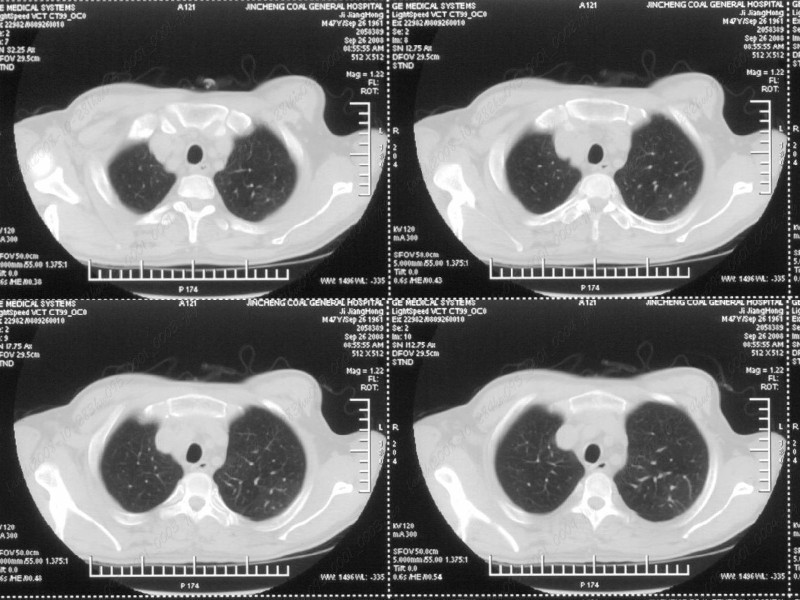

男性,47岁。胸部不适一年,ct检查发现右胸膜下结节。http://www.radida.com/bbs/forum.php?mod=viewthread&tid=46094

图像很清,资料很全。工作做的很细,向您学习!观阁下的强化图像发现,您们强化后扫描时间挺早,延迟时间大约在16—18秒之间吧。估计目的是为了观察肺动脉及分支的情况。但现有的资料并不能提示动脉栓塞改变。建议楼主可在机器上仔细观察,或许会有异常发现。另外,个人感觉右侧应为肺内结节而非胸膜结节。考虑肺内良性小结节,炎性假瘤可能性大。

右下肺前胸膜下小结节,强化不明显。建议定期观察!

病灶周围似有纤维化征像,增强明显强化,但中央可见点状低强化区,考虑慢性病变可能如炎性假瘤等,病灶边缘部分毛糙有切迹,双侧胸腔少量积液影,不除外恶性

结节未见明显强化,局部胸膜增后粘连,内缘纹理影增重伴小围星灶,局部胸膜下小三角状实变影,尖端见纤维索牵扯征,综合考虑炎性病变,有增殖表现,不出外tb灶

右肺中叶外侧段胸膜下结节状病灶,性质待定(不排除周围型肺癌可能)。

右前胸膜下小结节,边缘有小纤维条索影与胸膜粘连,考虑如炎性假瘤之类慢性病变可能。期待二周后的结果。

小结节的周围似乎与斜裂的走行有关,边缘分界不很清楚,与侧胸膜关系密切,有轻度强化,不能除外恶性,建议密切观察。

汇报临床诊断:右肺动脉分枝栓塞

右肺静脉充盈缺损,左心房体积小,右肺动脉远端动脉充盈缺损,右肺血管影细小,考虑;右肺动脉远端栓塞.